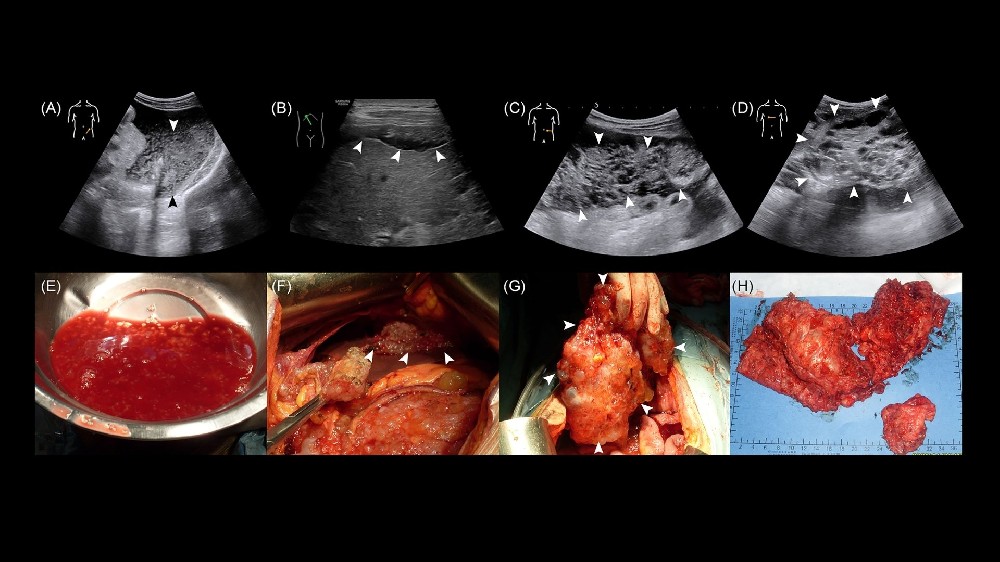

假性腹膜肌瘤 (PMP) 診斷 涉及多方面的方法,以準確評估該疾病的程度和性質。診斷方法很全面,包括:

活檢: 核心針切活檢是常見的方法。對於 PMP,細胞切除手術可對組織進行病理檢查,確保診斷的準確性。

成像技術: PET-CT 和 MRI 掃描可提供腫瘤生長及其對周圍器官影響的詳細影像。這些方法對於分期、判定 PMP 的擴散性和侵襲性至關重要。

手術: PMP 治療的基石是細胞復原手術結合腹腔內熱療化學治療 (HIPEC)。這種積極的方法旨在盡可能移除腫瘤塊,並直接在腹腔內使用加熱化療針對殘留的癌細胞。